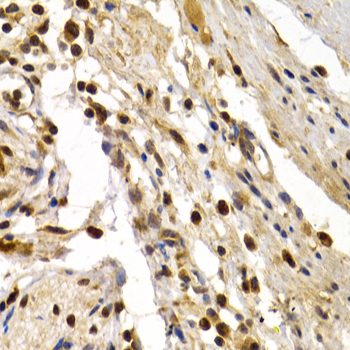

Immunohistochemistry of paraffin-embedded human colon damage using TFDP1 antibody at dilution of 1:200 (400x lens).